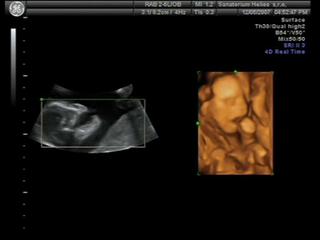

@valmark Já na 3D byla s klukem a to byla paráda, jak tam byl samotnej. Teď s klukama jsem šla taky, ale spíš jen proto, abych měla pro ně stejný fotečky jako pro Karímka.. kluci byli příčně, každej s hlavou na opačný straně, tak mám fotku jednoho s nohou toho druhýho v obličeji..asi prvních 5minut bylo něco poznat, ale pak se tam šmrdolilo pořád nějak moc rukou a nohou najednou, byla to taková změť , že se nic moc nedalo poznat. Ne že bych byla tak moc zklamaná, ale asi bych do toho s dvojčatama znova nešla..Zkusím tu pěknou fotku někde vyhrabat a poslat na ukázku..

Jinak my na tom 3D utz byli a taky bych ho ozelela. U tech dvojcatek nic moc,vsechno se tam mele pres sebe,ze tam neni nic moc poznat. Takze z tech fotek jsme rozeznali maximalne oblicej a zbytek byl takovej maglajs zlute hmoty🙂

@atreides Byla jsem přesně ve 24+0tt. Každýho chlapečka mám jednou vyfocenýho a ani jsme si nemohli z fotek vybírat, prvních 5minut sestřička chytla každýho kluka jednou a pak už nic..jen chumel rukou a nohou ☹

Tak tohle jsou moji chlapečci..na tý druhý fotce je vidět nožička prvního chlapečka, kopal bráchu do obličeje 😀